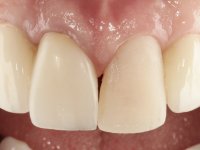

Paciente do sexo feminino, com 36 anos de idade, não fumadora. Apresentava o dente 1.1 com uma tonalidade mais escura que os dentes adjacentes. Feito o exame imagiológico, observou-se que o dente 1.1 tinha tratamento endodôntico, a paciente tinha 3 implantes colocados, dois no local dos dentes 1.2 e 2.2 e o outro no 4.6. A paciente tinha sido tratada ortodonticamente, apresentava um fenótipo gengival médio e uma boa higiene oral. Após 5 anos da primeira intervenção a paciente apresenta-se na consulta com sintomatologia infeciosa compatível com uma peri-implantite nos implantes 1.2 e 4.6. Após exame clínico, foi confirmada imagiológicamente. A perda óssea vertical tinha mais de 4mm nas duas situações.

Primeira Fase.

O dente 1.1 foi preparado para uma coroa total, o afastamento gengival foi feito com caolino comprimido pela restauração provisória. A impressão foi feita com uma técnica de dupla mistura com dupla viscosidade. No laboratório foi confecionada uma coroa com infraestrutura em Zr revestida por cerâmica. A coroa foi cimentada em boca com cimento de ionómero de vidro reforçado por resina.